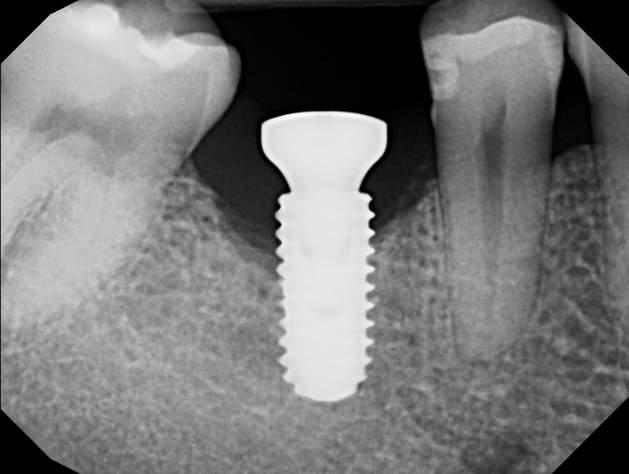

The LAPIP protocol offers a minimally invasive, laser-based method for treating peri-implantitis—the inflammation and bone loss that threatens the stability of dental implants. Using the same PerioLase® MVP-7™ technology as LANAP, LAPIP precisely targets infected tissue and harmful bacteria surrounding the implant while protecting healthy gum and bone. This allows the body to naturally rebuild lost support and helps save implants that would otherwise be at risk of failure. With no cutting or sutures required, LAPIP provides a gentle, highly effective alternative to traditional peri-implant surgery.

LAPIP™ (Laser-Assisted Peri-Implant Procedure) is a minimally invasive laser treatment designed to save ailing or failing dental implants caused by peri-implantitis. Using the PerioLase® MVP-7™ Nd:YAG laser, the protocol targets inflamed, infected tissue and titanium corrosion contaminants while preserving healthy gums and bone. This tissue-sparing approach promotes bone regeneration around the implant and offers a more comfortable treatment with less bleeding, swelling, and downtime than traditional surgery.

Because LAPIP treats the implant site without cutting or sutures, patients typically experience shorter healing times and fewer follow-up visits, helping keep overall treatment costs lower.

Removing and replacing a failing implant can require multiple surgical steps, bone grafting, and several months of healing, which significantly increases both time and cost.